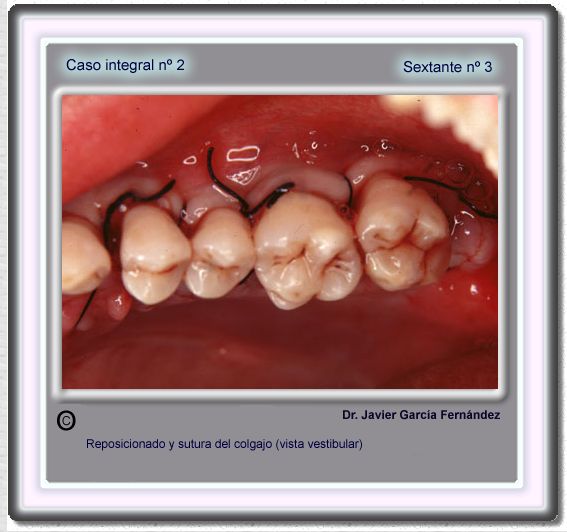

image 43